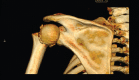

Introduction: Posteriorly dislocated humeral head fracture has a great implication, as it is associated with high risk of avascular necrosis, limited access through the deltopectoral approach, and posterior approach to the posteriorly dislocated humeral fracture increases the risk to the remaining blood supply.

Technical tip: Posteriorly dislocated humeral fracture is approached through deltopectoral approach. Schanz pin is inserted into the humeral head to achieve purchase in the humeral head. Applying laterally directed force the humeral head is disengaged from the lateral margin of glenoid. A rotatory force then repositions the humeral head into a congruous position. Open reduction internal fixation is then carried out in a standard fashion.

Conclusion: Retrieving the humeral head from the posteriorly dislocated position in patients with posterior fracture dislocation of the shoulder can be challenge to a trauma surgeon. With this novel technique, humeral head is reduced through deltopectoral approach without increasing the risk to the remaining blood supply.